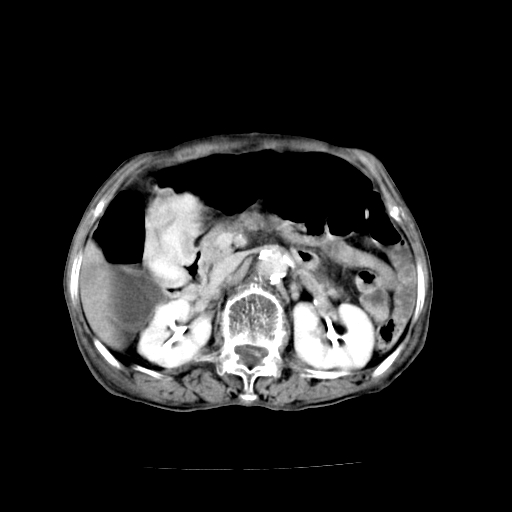

标题: CT19149:女,68岁,腹胀、恶心两周。 [打印本页]

女,68岁,腹胀、恶心两周,先做ct平扫,当时家属不同意强化,6天后家属要求增强扫描。

1)胃窦壁厚,考虑胃窦癌?建议行胃镜检查。 2)局灶性脂肪肝。

1)不排除胃窦癌;建议行胃镜检查。 2)局灶性脂肪肝。腹水。

考虑:胃窦ca,腹水,脂肪肝